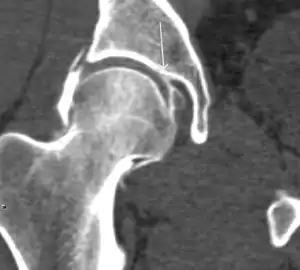

Synovial chondromatosis can be confidently diagnosed by X-ray when calcified cartilaginous chondromas are seen. However, other synovial proliferative processes, such as pigmented villonodular synovitis, require MRI for accurate diagnosis, although noncalcified synovitis can be suspected in radiographs by indirect signs, such as soft tissue swelling and/or erosions in the femoral head, femoral neck, or acetabulum (Figure 7).[1]

Figure 7:

Axial CT image of pigmented villonodular synovitis eroding the posterior cortex of the femoral neck.[1]

In synovial proliferative disorders, MRI demonstrates synovial hypertrophy. In the case of PVNS, characteristic foci of low signal intensity related to hemosiderin deposition are better seen on gradient echo T2* images (Figure 7). In the case of synovial osteochondromatosis, the synovial hypertrophy is accompanied by intermediate signal cartilaginous loose bodies and/or low signal calcified loose bodies.[1]